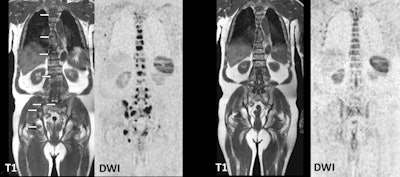

He offered ECR 2021 virtual attendees several examples of SLLs and CLLs in which lymphadenopathy showed very little uptake of FDG and abnormalities were almost impossible to see on CT. DWI-MRI, however, "beautifully" showed evidence of lesions in the liver and in the stomach. "Therefore, the histological subtitle of lymphoma is of high relevance for imaging," Mayerhöfer said. "In those lymphomas, which should not undergo PET/CT, according to the guidelines, DWI-MRI was better than all techniques including contrast-enhanced CT."

On the other hand, previous studies have shown that whole-body MRI can perform very well with aggressive lymphomas. "Altogether [MRI] is good, but not quite as good as FDG-PET/CT, as we found in our study of different lymphoma subtypes," Mayerhöfer said. "We saw that it is really the lymph nodes that are a problem. The sensitivity of MRI for nodal disease is not quite as good as FDG-PET/CT, whereas for extranodal disease, [MRI's] performance is almost perfect, almost on par with PET."